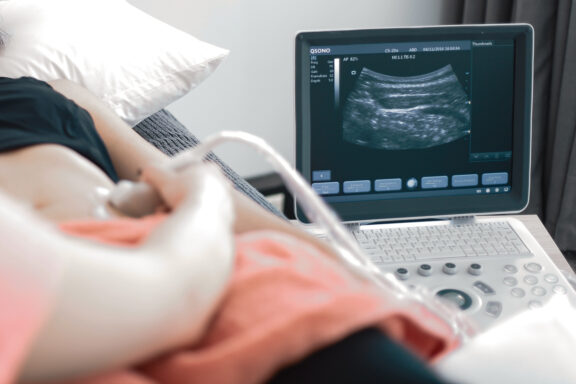

The most unique and important part of a post-natal assessment at The Studio is the assessment of your deep core muscles and pelvic floor via the real time ultrasound.

• You actually get to see your “core” muscles in action and learn how to effectively switch them on. This may feel somewhat difficult post-partum as your proprioception (awareness) of these muscles may be slightly dampened, particularly if you have had a caesarean section (major abdominal surgery).

• We can see your deep core muscles in different positions relative to your functional needs such as sitting and squatting.

• Your Pelvic Floor is assessed!! So important after your pregnancy journey regardless if you have had a vaginal birth or caesarean section.  Regardless of how your pregnancy journey ends you have still spent 9 months with your baby placing extra pressure on your pelvic floor muscles. It is important to assess the strength and endurance of these muscles post-partum so we can give you some basic pelvic floor strength exercises to get you safely back to your pre-baby function, especially if you are planning on having more bubbas!

• Once you can visualise these muscles in action your awareness of these areas increases allowing you to gain the most out of your exercise and everyday activity whether it is bending down to pick up your baby or holding yourself elegantly in double leg table top during your favourite Pilates class.